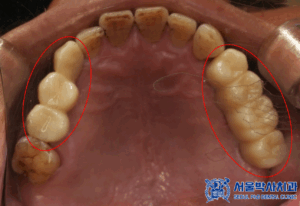

식립한 임플란트가 잘 치유되어

보철 작업을 시작하였습니다.

보철 작업은 디지털 장비를 활용해

정밀하게 진행되었으며,

환자분의 자연치아와

유사한 기능과 형태를

복원할 수 있도록 최선을 다했습니다.

먼저 맞춤형 지대주와 함께

임시치아를 만들어 적응 기간을

거칠 수 있도록 하였습니다.

임시치아로 적응 기간을 거친 뒤

환자분께서는 불편함 없이

잘 쓰셨다고 하셔서

최종 보철 작업을 진행하였습니다.

주변 치아와의 색상 및 형태를

세심하게 맞춰 자연스러운 조화를

이루도록 완성하였습니다.

이렇게 본원의 원내기공소에서

직접 제작한 개인 맞춤형 보철물을

전부 세팅해드렸습니다.

마무리 후 사진입니다.